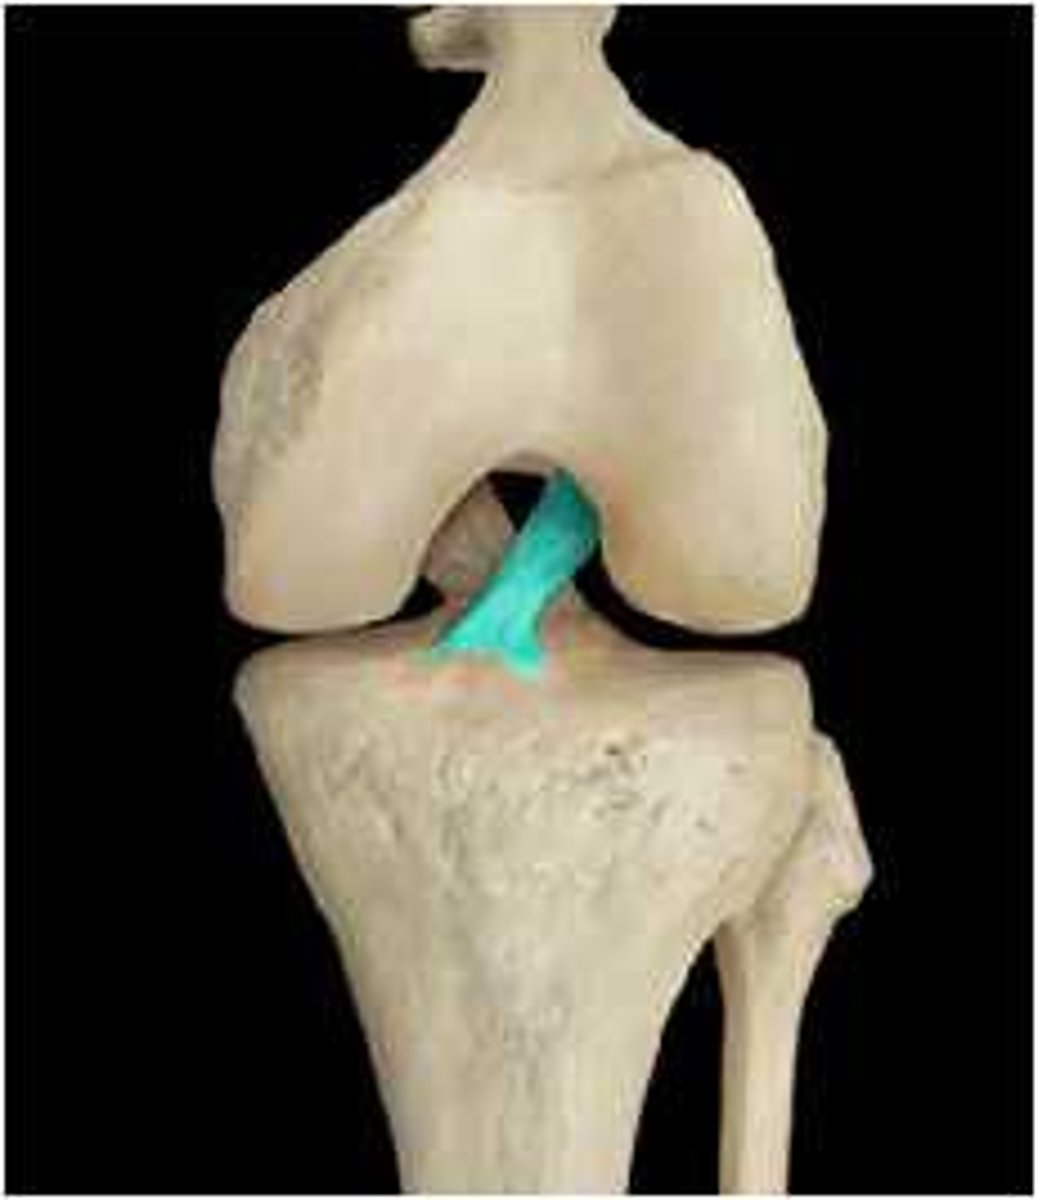

Posterior Cruciate ligament

Anterior Cruciate Ligament (ACL)